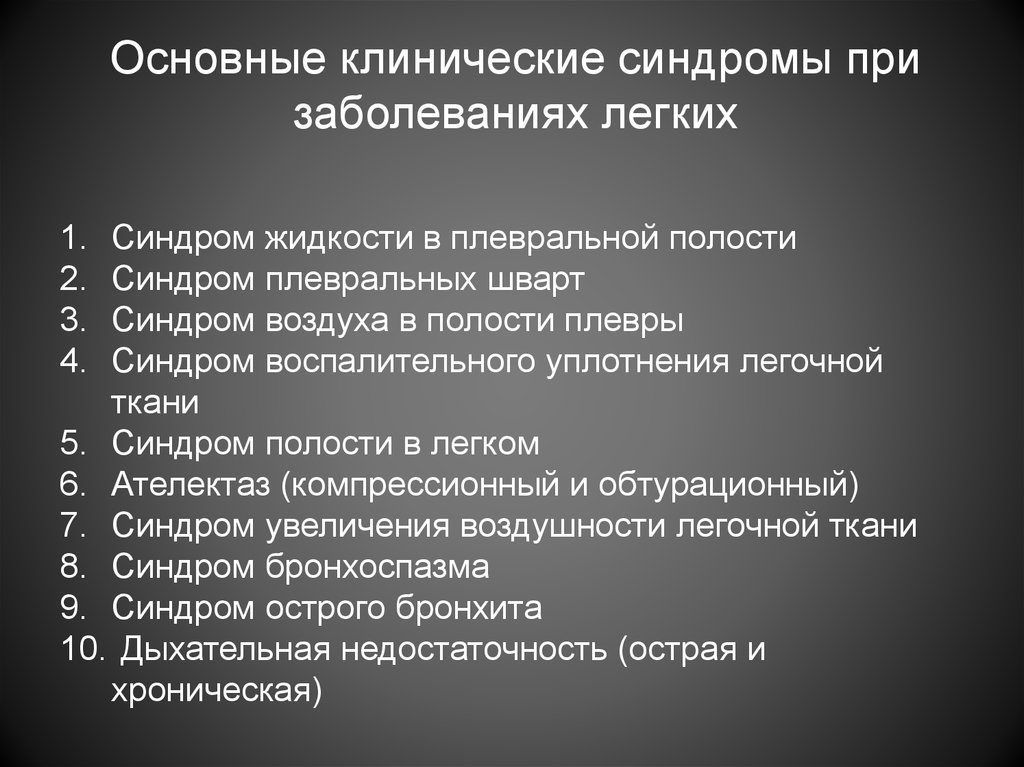

Дифференциальная диагностика заболеваний плевры